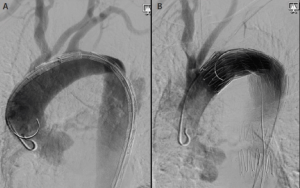

What we do know is that early treatment of type B aortic dissection within the first 48 to 72 hours, or even within a week, is associated with an increased risk of retrograde type A dissection—at least when TEVAR is used to manage patients with an acute complicated process (Figure 1). This dreaded catastrophe, which is not universally fatal and not exclusively due to the endoprosthesis, may occur at a rate as high as 3% to 4%.3-5 Based on published meta-analyses, approximately 23% of these cases were diagnosed during the procedure (8%) or immediately periprocedurally (15%), with associated mortality rates of 70% and 50%, respectively.3 This is compared to an estimated mortality rate of 30% for cases of retrograde type A dissection diagnosed after hospital discharge.

Figure 1. A 68-year-old woman with an acute type B aortic dissection. The left anterior oblique aortogram with an endograft in the aortic arch just beyond the left carotid artery origin prior to deployment. The ascending aorta is normal with a guidewire and flush catheter against the outer anterior wall (A). Aortogram postdeployment of the endograft with a flush catheter within the true lumen of the ascending aorta displaced away from the anterior wall by a false lumen caused by retrograde type A aortic dissection. The patient went to the operating room for open repair of the ascending segment and recovered uneventfully (B).